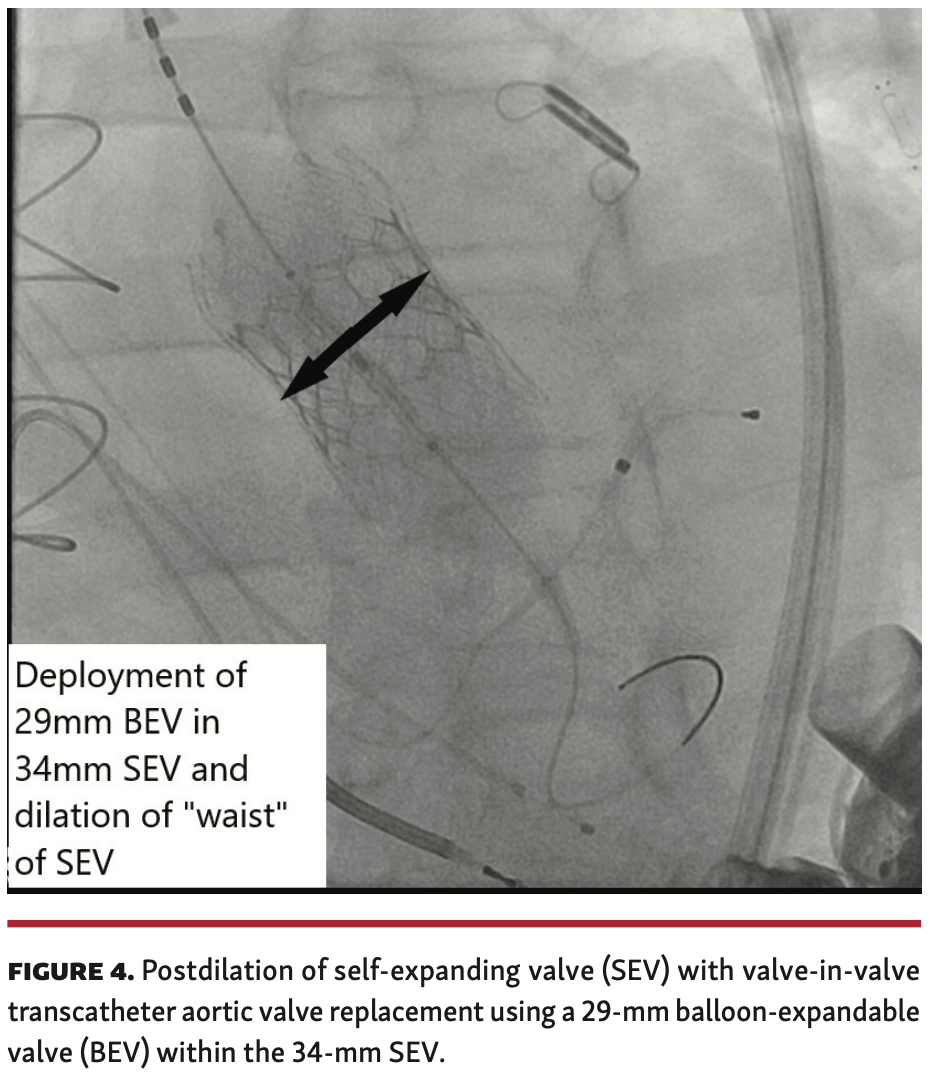

Procedural technique. A 34-mm Evolute SEV (Medtronic) is advanced over a double-curve Lunderquist wire (Cook Medical) and positioned within the aortic annulus. Aortic root injections are performed. Without pacing, the valve is slowly deployed to 80% with repeated aortic root injections and transthoracic echocardiographic evaluation. The valve is observed in this position for 5-10 minutes to see if it appears to be migrating into the left ventricle. The LVAD flow rate is slowed and with rapid pacing the valve is then released (Figure 1 and Figure 2). Rapid pacing is discontinued. Over 5-10 minutes, the LVAD flow rate is ramped up to baseline rotations/minute with continuous observation under echocardiography and cine angiography. Procedural variables are listed in Table 2. All 4 of our patients underwent TAVR with a 34-mm Evolut SEV (Medtronic). For patient 4, who developed moderate paravalvular leak (PVL) with ventricular migration of the SEV, we deployed a 29-mm Sapien 3 BEV (Edwards Lifesciences) within the SEV, with fluoroscopically visible expansion of the “waist” of the SEV (Figure 3 and Figure 4).

Four consecutive patients with pre-existing LVADs received TAVR for severe AR. Baseline clinical characteristics are presented in Table 1. All 4 patients received a 34-mm Evolut SEV. One patient underwent valve-in-valve TAVR with a 29-mm Sapien 3 BEV during the index TAVR. There was no central valvular AR after TAVR in any of the patients. Patient 4 had a moderate to severe PVL that improved after valve-in-valve TAVR with 29-mm BEV, but continued with persistent mild to moderate PVL. Procedural characteristics are outlined in Table 2.